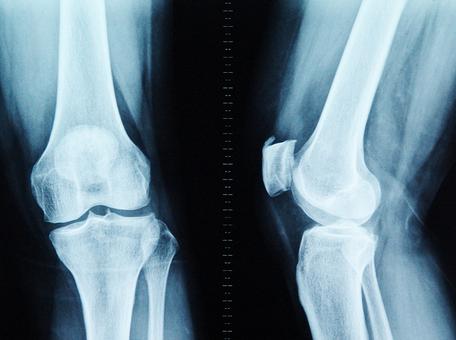

骨刺是骨质增生的主要表现,但是严谨来说,医学上并没有称为骨刺的疾病,骨刺就是一种关节和骨骼正常退变老化的表现。40岁后,90%的人负重关节或多或少产生增生性改变,长出骨刺。一般来说,骨刺悄悄生长并不影响生活,患者并无临床表现,只有当骨刺发展到一定程度,开始累积压迫到周围神经和血管,并造成局部无菌性炎症时,才会出现肿胀、积液、疼痛等临床症状。

在人体的“骨骼大厦”中,胶原蛋白是钢筋,钙、镁、磷等骨质就是水泥。30岁后,胶原蛋白流失加剧,胶原框架老化变细、变脆甚至断裂,出现缺口;钙、镁、磷等骨质无法正常沉积在骨骼上,从缺口中游离出来;随着肢体的活动和负重,游离的骨质慢慢堆积在活动频繁、承重量大的关键部位(如颈椎、腰椎、膝关节、足跟),骨刺由此产生。